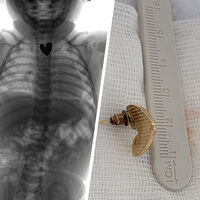

Ребенок с подозрением на проглоченное инородное тело был доставлен в больницу из одного из районов Бурятии. В ходе обследования выяснилось, что в верхней области пищевода младенца застряло инородное тело в форме сердца размером 1,5 см.

«Из-за особых свойств инородного тела (сережка-гвоздик с острым наконечником, сердцевидная форма), оно было низведено в желудок, чтобы избежать травм. Мы не могли рисковать жизнью ребенка, поэтому принято решение провести извлечение инородного тела из желудка хирургическим путем», — сообщил врач-хирург ДРКБ Вячеслав Данчинов.

Инородное тело удалось успешно извлечь, ребенок находится в отделении реанимации, его состояние медики оценивают как стабильно тяжелое.